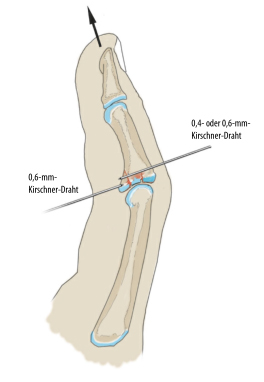

Стальную иглу диаметром 0,4 или 0,6 мм вводят дорсально в ладонный отломок. Ладонную кору необходимо прорвать, но только на несколько миллиметров, чтобы избежать раздражения сухожилий сгибателей.

2) Чем выше нестабильность сустава (например, перелом III типа), тем раньше следует использовать блокирующий штифт. (Как показано ниже)